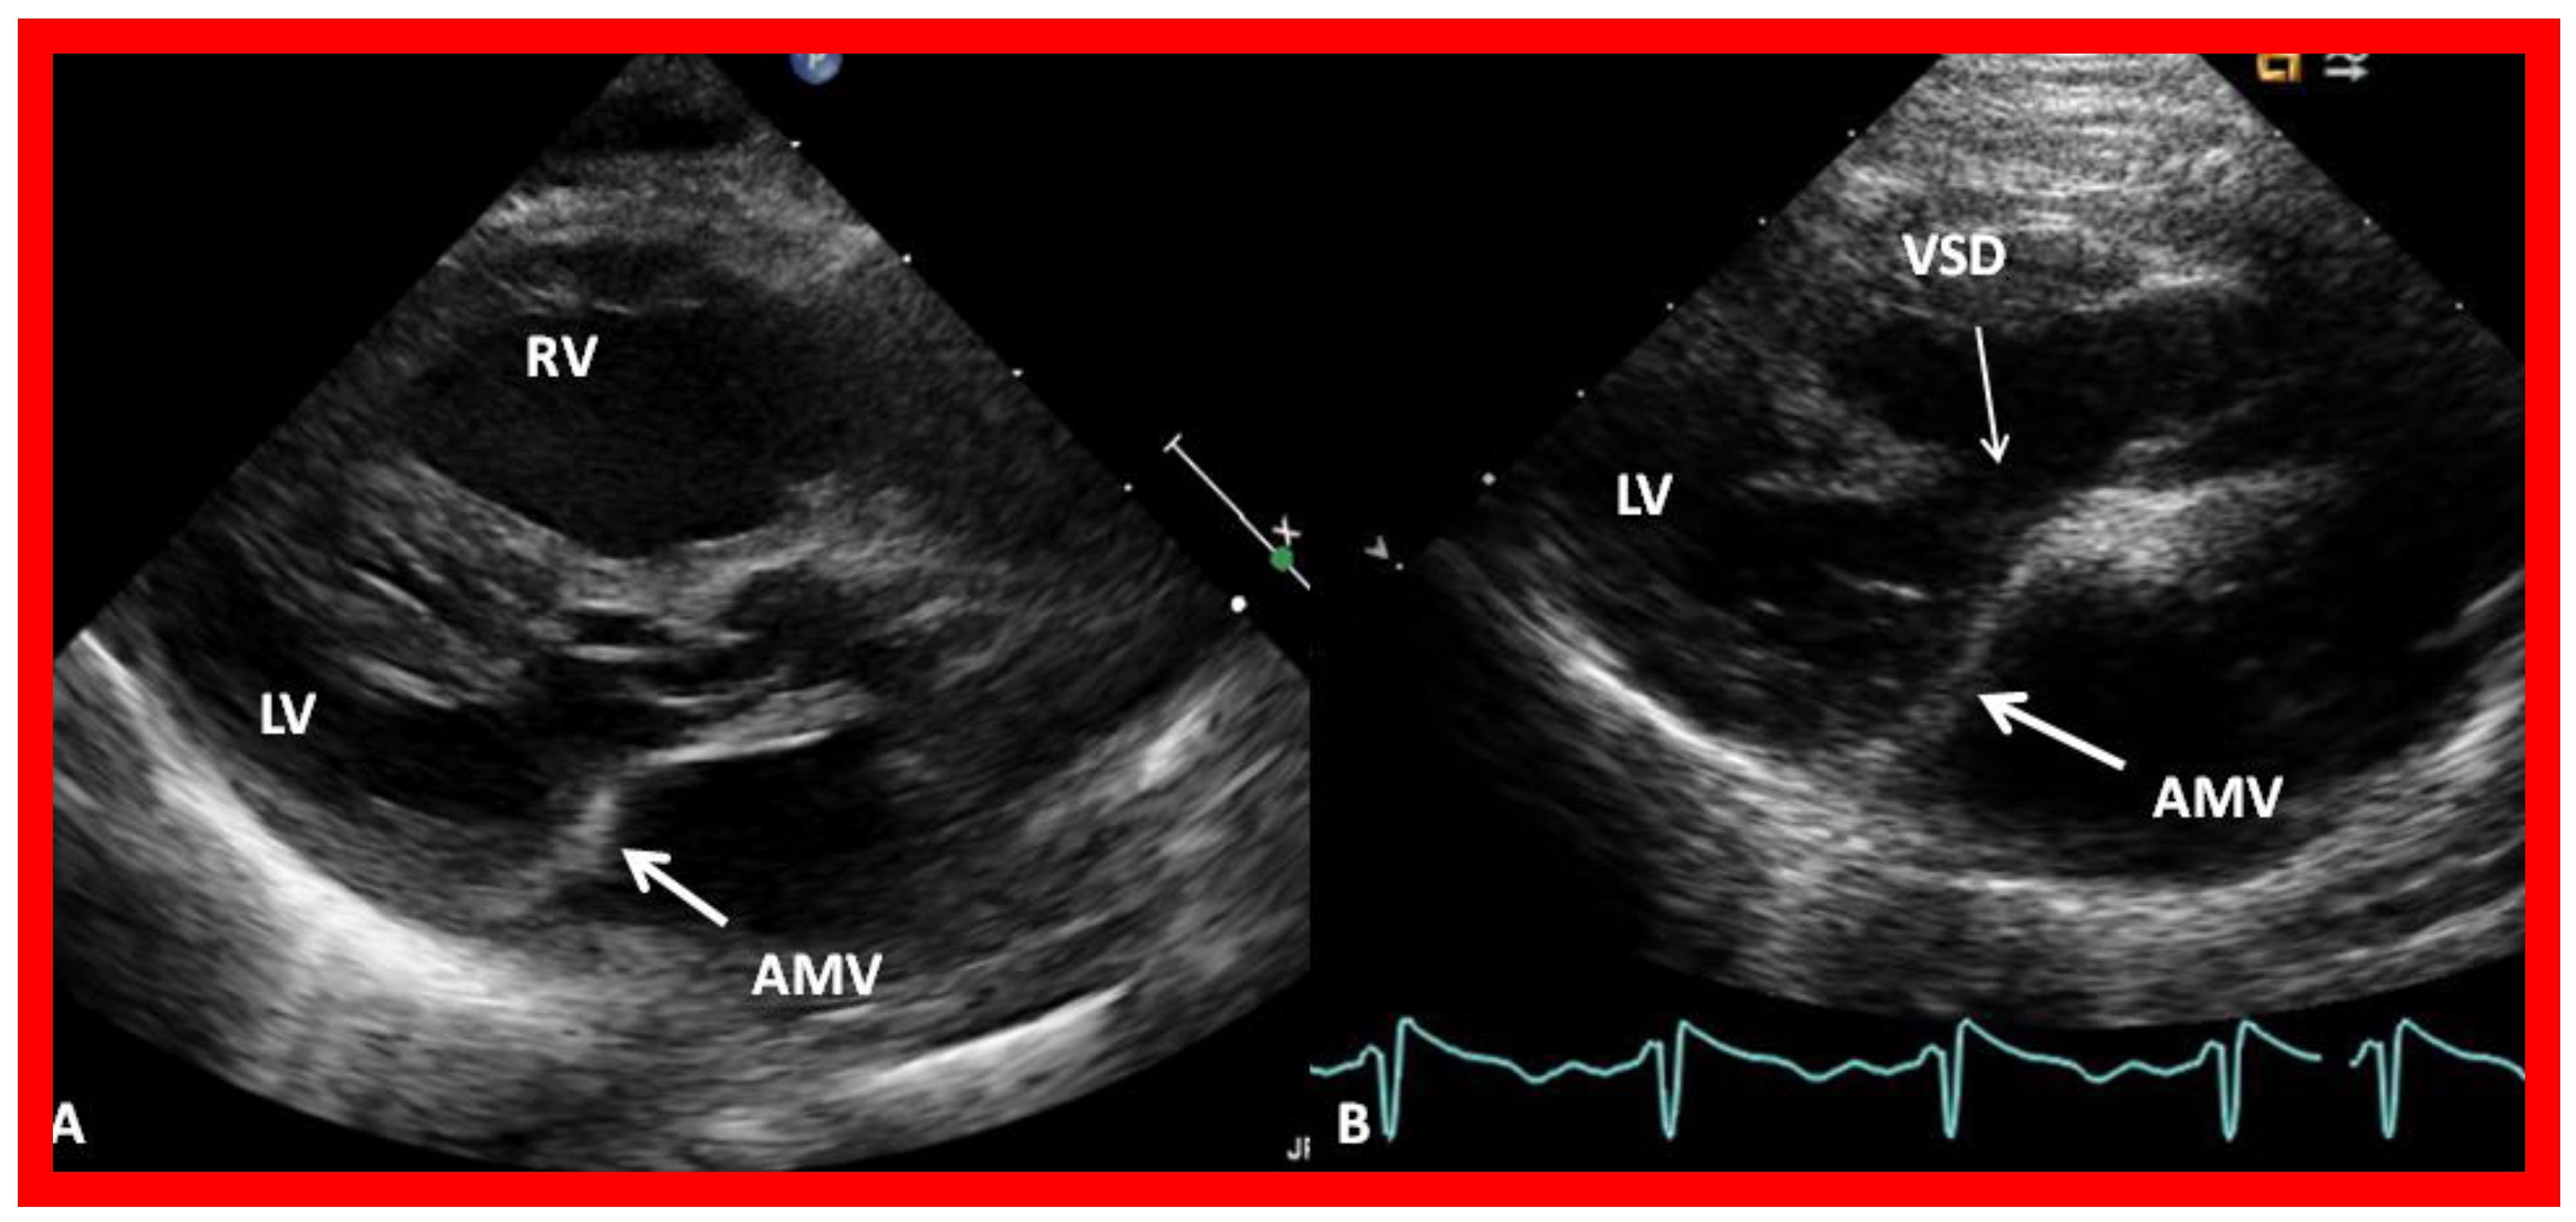

8. Echocardiogram